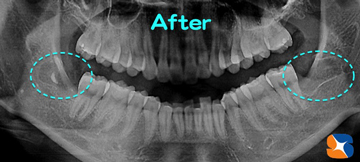

消毒のため、抜歯から5日目の本日来院。その結果、「痛みも腫れもほとんどない。

アゴの痛みもなく、ツバを飲んでも痛まない。痛み止めも飲まなくても大丈夫」とのことでした。

が決まります。今回のケースは、正に“ウルトラC”でした。出発まで残りあと僅かですが、最後まで責任をもって経過を見ていきます。本当によく頑張られました。